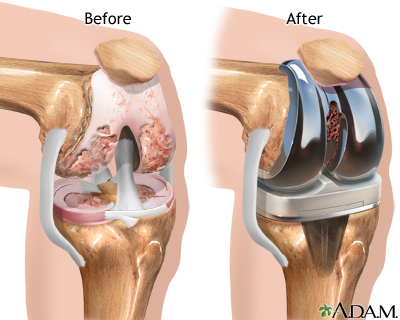

Joint Replacement

At Pluto Super Speciality Hospital and Trauma Center, our Joint Replacement specialists provide expert care for patients with arthritis, joint injuries, and degenerative conditions. Using advanced techniques, we perform knee, hip, and shoulder replacements to alleviate pain, restore mobility, and help patients return to their daily activities with improved quality of life.